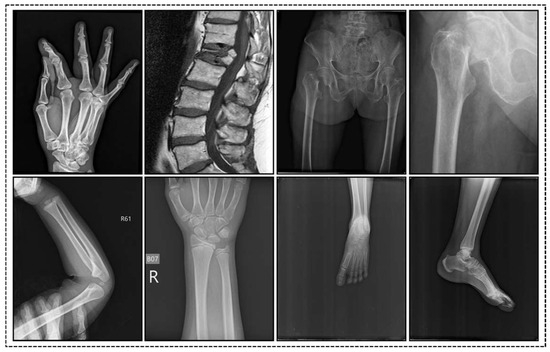

Such meticulous organization ensures a balanced and thorough evaluation of the proposed automatic fracture detection system. The dataset, which is publicly accessible on Kaggle, serves as a crucial resource for training and assessing the model’s performance in identifying fractures in clinical settings. Figure 2 shows fractured and non-fractured images of the training sample.

Figure 2. The first row displays sample images of fractures, while the second row shows sample images of non-fractures.